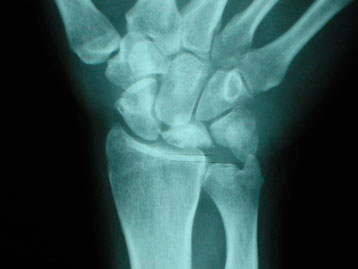

La resonancia nuclear magnética (RNM) es la prueba diagnóstica más útil porque permite el diagnóstico precoz de la enfermedad de Kienböck y evalúa los resultados tras la cirugía (figura 5). La tomografía axial computarizada (TAC) permite valorar mejor la estructura ósea y un estadiaje más preciso.

I: morfología y densidad radiológica del semilunar normal. En RNM sí se aprecia sí se aprecia de distinta condensación debido a la falta de sangre (figura 5).

Figura 5: enfermedad de Kienböck en estadio precoz (en la RNM el semilunar se ve de color negro)